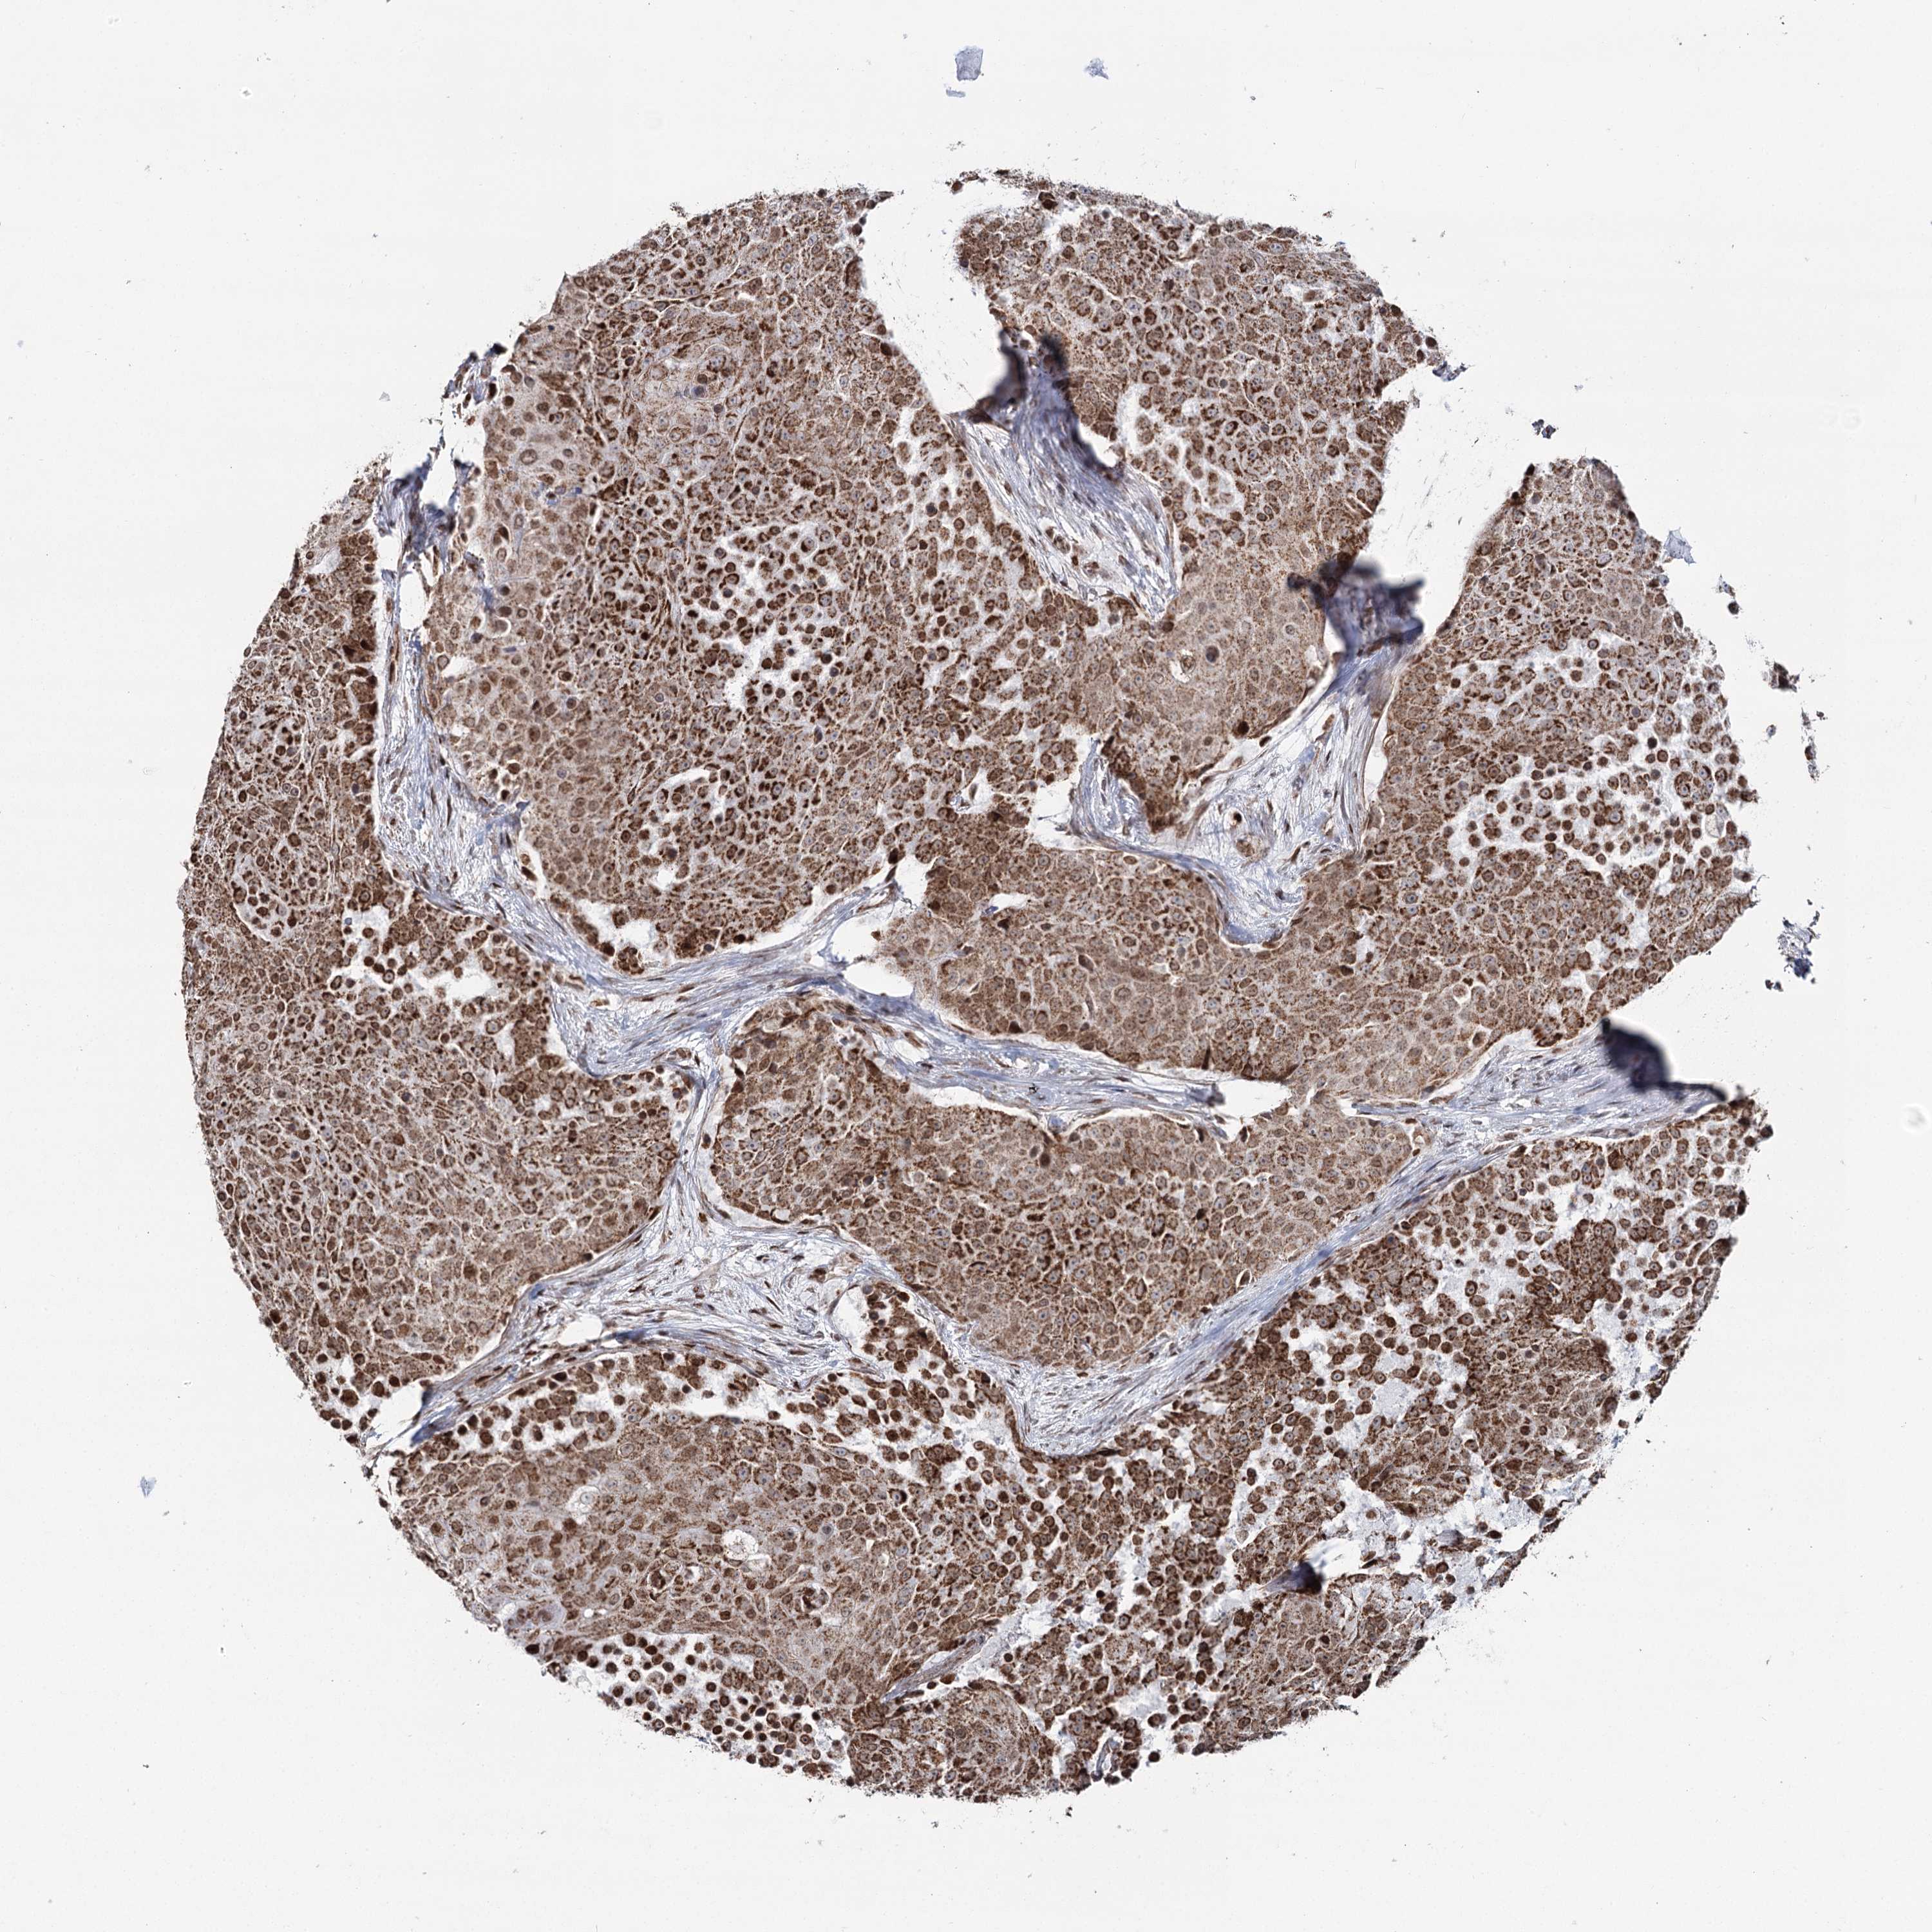

UROTHELIAL CANCER - Protein expressioni

A mouse-over function shows sample information and annotation data. Click on an image to view it in a full screen mode. Samples can be filtered based on level of antibody staining by selecting one or several of the following categories: high, medium, low and not detected. The assay and annotation is described here.

Note that samples used for immunohistochemistry by the Human Protein Atlas do not correspond to samples in the TCGA dataset.

Antibody stainingi

Antibody staining in the annotated cell types in the current human tissue is reported as not detected, low, medium, or high, based on conventional immunohistochemistry profiling in selected tissues. This score is based on the combination of the staining intensity and fraction of stained cells.

Each image is clickable and will lead to virtual microscopy that enables deeper exploration of all samples and also displays staining intensity scores, fraction scores and subcellular localization as well as patient and tissue information for each sample.

Antibody HPA038484

Antibody HPA038485

Staining

High

Medium

Low

Not detected

Intensity

Strong

Moderate

Weak

Negative

Quantity

>75%

75%-25%

<25%

None

Location

Nuclear

Cytoplasmic/membranous

Cytoplasmic/membranous,nuclear

Urothelial carcinoma, High grade

Urothelial carcinoma, Low grade

Urothelial carcinoma, NOS